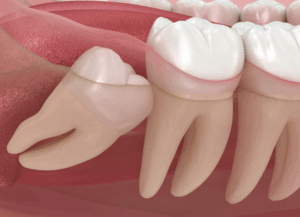

3. 歯並びへの悪影響

横向きに生えてきた親知らずが手前の歯を前へ前へと押し続けることで、時間をかけて歯並び全体が少しずつ乱れてきてしまうことがあります。

特に一度矯正治療できれいにした歯並びが、後から生えてきた親知らずの影響で再びガタガタになってしまう「後戻り」の原因となることもあります。